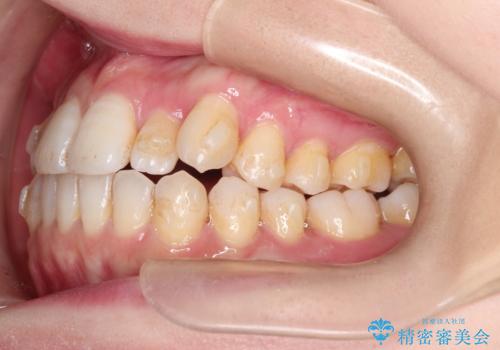

インビザラインで八重歯の矯正

- 八重歯を治したいとのことで、来院されました。

インビザラインにて、上顎の歯と歯の間をわずかに削り、並べる計画としました。

使用時間を守っていただけたので、比較的スムーズに矯正を終了することができました。